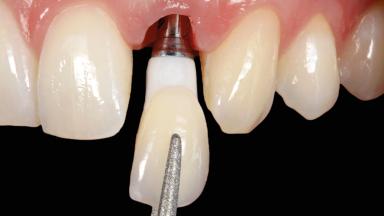

In this case, Arndt Happe describes how he achieved a stable outcome at 5 years by giving careful attention to the coronal aspect of the transmucosal area of the provisional, creating a slim emergence profile.

A healthy 31-year-old female patient presented with a failing maxillary left lateral incisor crown. The crown regularly loosened, and the remaining tooth was neither restorable nor rational to treat. The patient had a high smile line, a medium soft tissue biotype with a compromised mesial papilla (shorter than the contralateral one), and a horizontal scar in the buccal soft tissue as a result of past periapical surgery.

| Biological | Screw-retained restorations with appropriate contours |

| Loading Protocol | Immediate |

| Implant-supported provisional restoration | Required, elevated esthetic and/or functional demands |